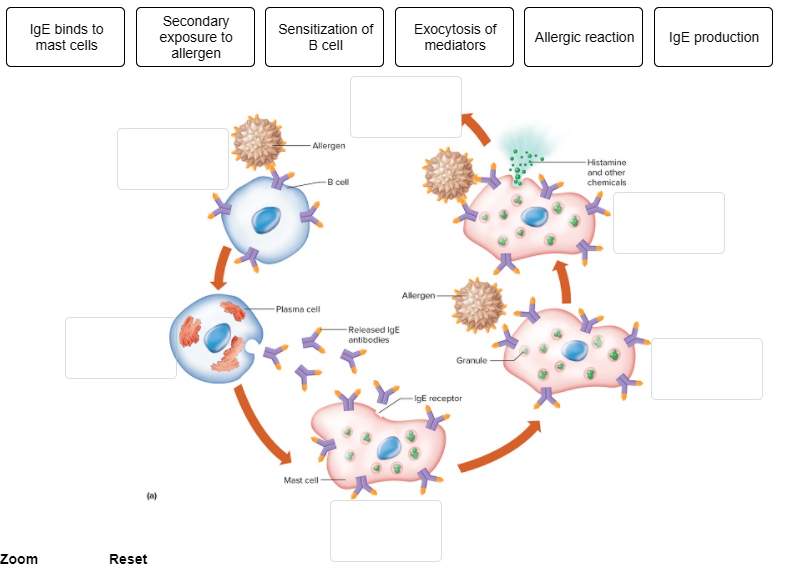

What class of immunoglobulin is involved in immediate-reaction allergic reactions?

Put the steps that occur during an immediate-reaction allergic response in the correct order.

Place the steps that occur during an immediate-reaction allergic response in the correct order.

1. Indicate the order of cell types involved in the response to the

first exposure to an allergen.

2. Antibodies attach to mast cells

via what part of the antibody structure?

3. With second exposure

to an antigen, the antigen molecules bind to __________.

1. Antigen-presenting cell, helper T cell, B cell, plasma

cell

2. Constant region

3. IgE on the mast cells